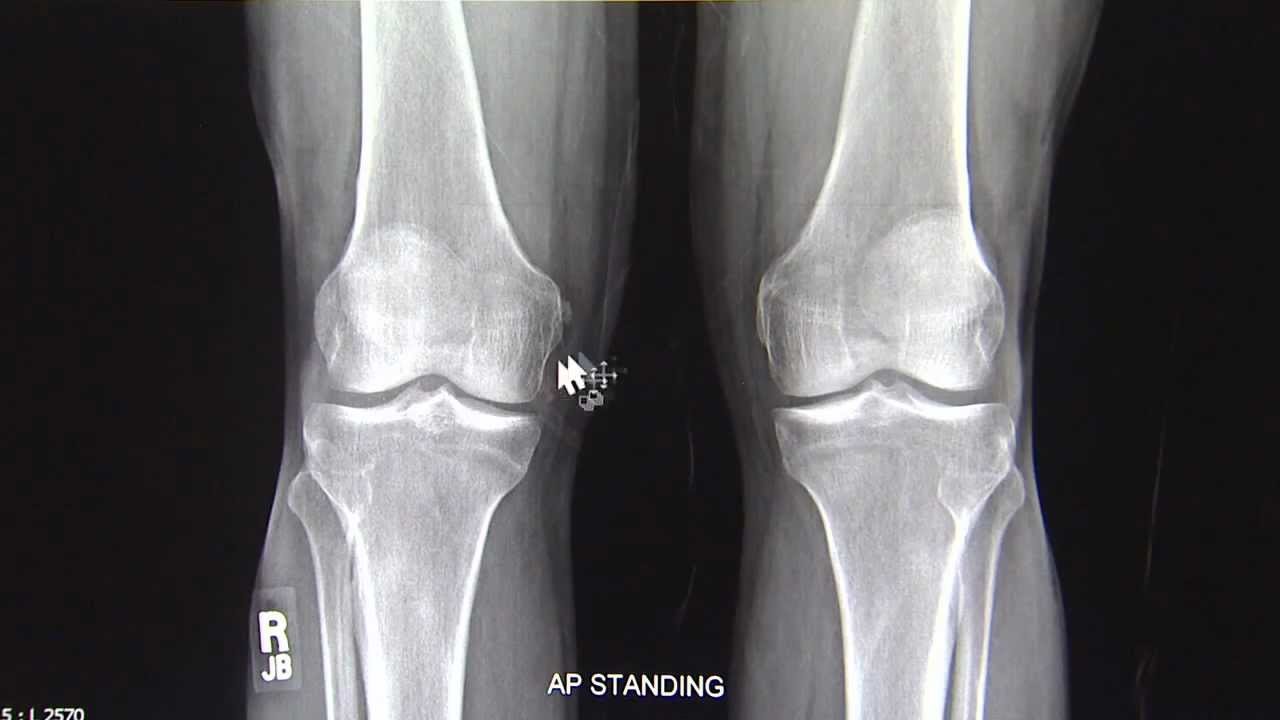

الأشعة السينية لتصوير العظام (Bone X-Ray).

يستعين الطبيب العظام بالأشعة السينية لتشخيص العديد من الأمراض وأيضًا كأحد خطوات ما قبل وأثناء وبعد الجراحة, ونبين استخداماتها فيما يلي:

- الكشف عن إصابات بالعظام مثل, العدوى البكتيرية, التهاب المفاصل الصديدية, النمو غير الطبيعي والتغيرات العظمية الناتجة عن حدوث خلل في التمثيل الغذائي.

- تشخيص خلع المفاصل وشروخ و كسور العظام.

- تعمل الأشعة السينية على إرشاد جراح العظام أثناء إجراء جراحة تركيب المفاصل الصناعية, وجراحة الرد المفتوح للكسور مع التثبيت الداخلي (Open Reduction Internal Fixation-ORIF ) وهي جراحة رد أجزاء العظام المكسورة إلى موضعها الصحيح باستخدام مثبت داخلي, جراحات إصلاح العمود الفقري وجراحات القدم مثل جراحة ابهام القدم الأروح و جراحة تثبيت مفصل الكاحل وغيرهم من جراحات العظام المختلفة.

- إظهار مدى استجابة العظام للعلاج بعد الكسور وصحة التئامها واستقرار شظايا العظام في المكان الصحيح لتكوين عظام جديدة.